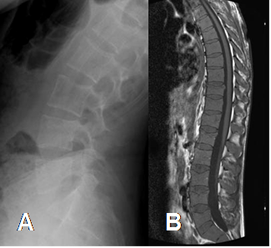

Fig 26. Mieloma múltiple.

A: RX lateral de columna. Signos de osteopenia generalizada.

B: RM sagital en T1. MO de las vértebras hipointensas, por infiltración tumoral.